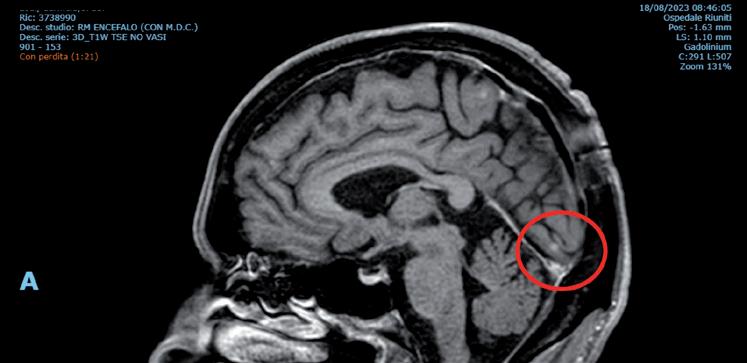

Alla RM encefalo effettuata nell’aprile 2022 compaiono nodularità in sede meningea lungo il profilo superiore del tentorio destro, la falce destra e la pachimeninge occipitale destra, con diametro massimo di 3 mm. L’esame citologico del liquor non ha evidenziato la presenza di cellule tumorali. La rivalutazione sistemica di malattia ha inoltre dimostrato una lieve progressione linfonodale mediastinica.

La paziente ha pertanto avviato una seconda linea di trattamento con T-DXd, ottenendo una progressiva riduzione delle lesioni meningee note ai successivi controlli mediante RM, fino ad arrivare a una situazione di stabilità che si mantiene tuttora a 24 mesi dall’avvio del trattamento (figura 1).

Figura 1. Immagini RM prima dell’avvio del trattamento e dopo 6 mesi.